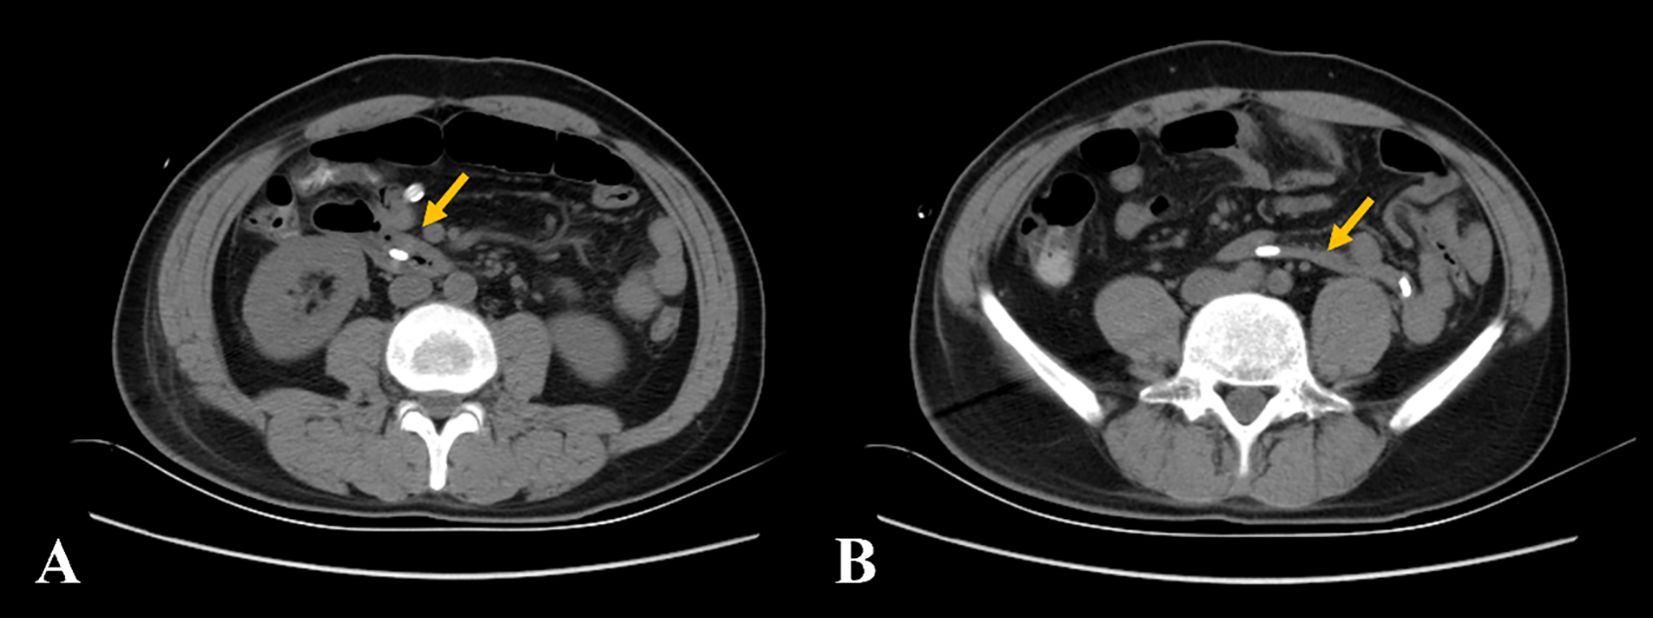

CT examination of the abdomen revealed marked thickening of the duodenal walls, and a strip-like, mixed-density lesion with fat attenuation was observed in the intestinal canal, measuring an average of 35 Hounsfield units (HU), which was blocking the duodenal duct. The proximal intestine was dilated. The third portion of the duodenum (transverse segment) and the proximal jejunum were located in the pelvis. Contrast-enhanced abdominal CT scans later revealed thickening of the duodenal walls with marked enhancement and a strip-like, mixed-density lesion with mild to moderate enhancement (density of 49 HU in the arterial phase and 61 HU in the venous phase). Moreover, part of the enhanced duodenal intestinal wall was stretched into the intestinal lumen. Fat attenuation was observed between the lesion and the intestinal wall, with mesentery blood vessels seen in enhancement, and the image showed incomplete intussusception (Figure 1). The mucosal layer of the lesion and the adjacent duodenal walls were seen unclearly on contrast-enhanced CT images.

Figure 1

CT scans show cross-sectional and coronal views of the abdomen. Panels A to E highlight a mass indicated by yellow arrows, with panel B also featuring the mass with fat attenuation by a red arrow. Panel C includes a star and panel F shows both yellow and white arrows highlighting specific regions within the abdomen.

Figure 1. (A–C) The non-contrast computed tomography showed a strip-like lesion with fat attenuation (red arrow) in the duodenal intestinal canal. The lesion obstructed the descending part of the duodenum, with significant dilatation (yellow asterisk). (D–F) The contrast-enhanced computed tomography showed the lesion with mild to moderate enhancement with incomplete intussusception, and mesentery and mesenteric blood vessels can be observed (white arrow). The proximal small intestine was located in the pelvic cavity (white asterisk).

CT exhibits sensitivity in detecting hamartomas and secondary complications associated with these lesions. Due to the small number of cases, few specific imaging findings were found. In many instances (4, 8, 9, 13, 14), the hamartomas were located at the duodenal bulb or the descending sections of the duodenum, and the enhancement of CT was heterogeneous. CT showed only marked thickening of the gastrointestinal wall when the hamartomas were small, and hamartomas that appeared as polypoid masses protruding into the lumen, mostly with proximal intestinal dilation or different degrees of intussusception when the hamartomas were larger. Because the Brunner gland is located in the submucosa, most duodenal BGHs can be covered by normal intestinal mucosa. Contrast-enhanced CT scans showed that the lesions were located within the intestinal cavity, and the mucosal layer was visible on the CT images. The coronal section revealed multiple layers of mucosa in the intestinal cavity, resembling “intussusception,” which may lead to misdiagnosis of intussusception on imaging (4, 8, 9, 13, 14). In this case, perhaps due to the large polyp, the mucosal layer of the hamartoma was unclear in relation to the mucosal layer of the intestinal wall, and the “illusion of intestinal intussusception” was not evident. However, the adjacent intestinal wall was stretched into the lumen of the intestine. The stretched intestinal wall showed mucosal enhancement in the contrast-enhanced CT. The mesentery and mesenteric blood vessels can be seen between the lesion and the intestinal wall, suggesting that this case was likely a combination of incomplete intussusception, rather than pseudo-intussusception caused by multiple mucosal folded between the lesion and the intestinal wall. It is necessary to identify whether there is a true intussusception on the image.

However, the hamartoma exhibited heterogeneous density on CT imaging, with fat attenuation within the lesion. It was relatively rare in previous reports (4, 8, 9, 13, 14). The duodenal BGH can contain mature adipocytes, and fat density can be seen in the tumor on CT imaging. Therefore, we hypothesized that the imaging finding of an elongated intraluminal mass lesion with heterogeneous density and fat attenuation in the duodenum should raise clinical suspicion for a pedunculated duodenal BGH, especially when accompanied by intussusception or obstruction.